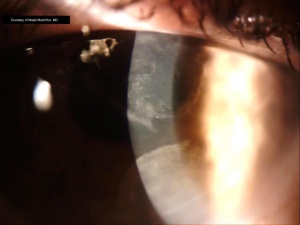

Wavelike plaques with well-defined borders are present, arising from the superior limbus and spreading toward the central cornea (figure 1). A granular texture with sclerotic scatter is visible on the corneal surface, and a subepithelial haze is sometimes appreciable (figure 2). No infiltrates or discrete inclusions are found. Fluorescein reveals a punctate staining pattern, also with distinct margins as visible with the slit lamp.[1][2][3] Atypical, elongated cells may be seen on confocal microscopy. These have a large nuclear-cytoplasmic ratio, loss of visible cellular borders, and hyperreflective nuclei.[1][2][15]